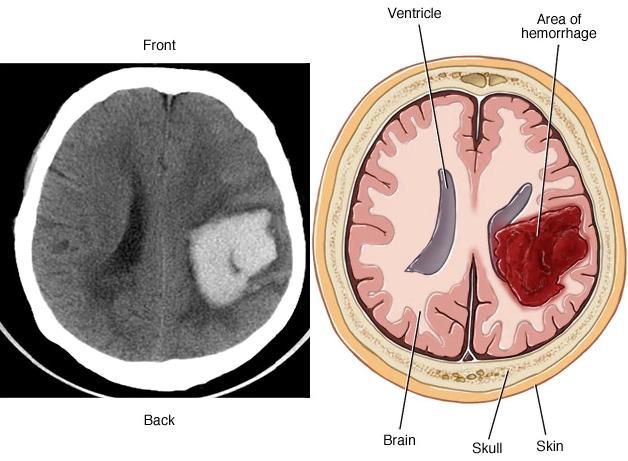

| Комп’ютерна томографія (КТ) | Забезпечує візуалізацію головного мозку для виявлення ішемічних змін та анатомічних аномалій судин. |